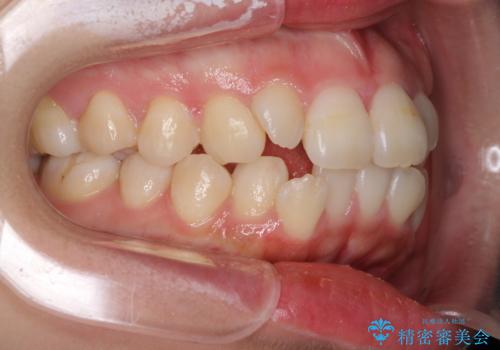

- 口元の突出感を気にして来院された患者様です。

診断の結果、上顎左右第一小臼歯4本抜歯により、叢生を解消するとともに口元を引っ込めていくことが望ましいと判断しました。

抜歯矯正による口元の改善にはワイヤー矯正が望ましいのですが、ダンサーとしての仕事を行っているため、インビザラインにて治療を行うこととしました。